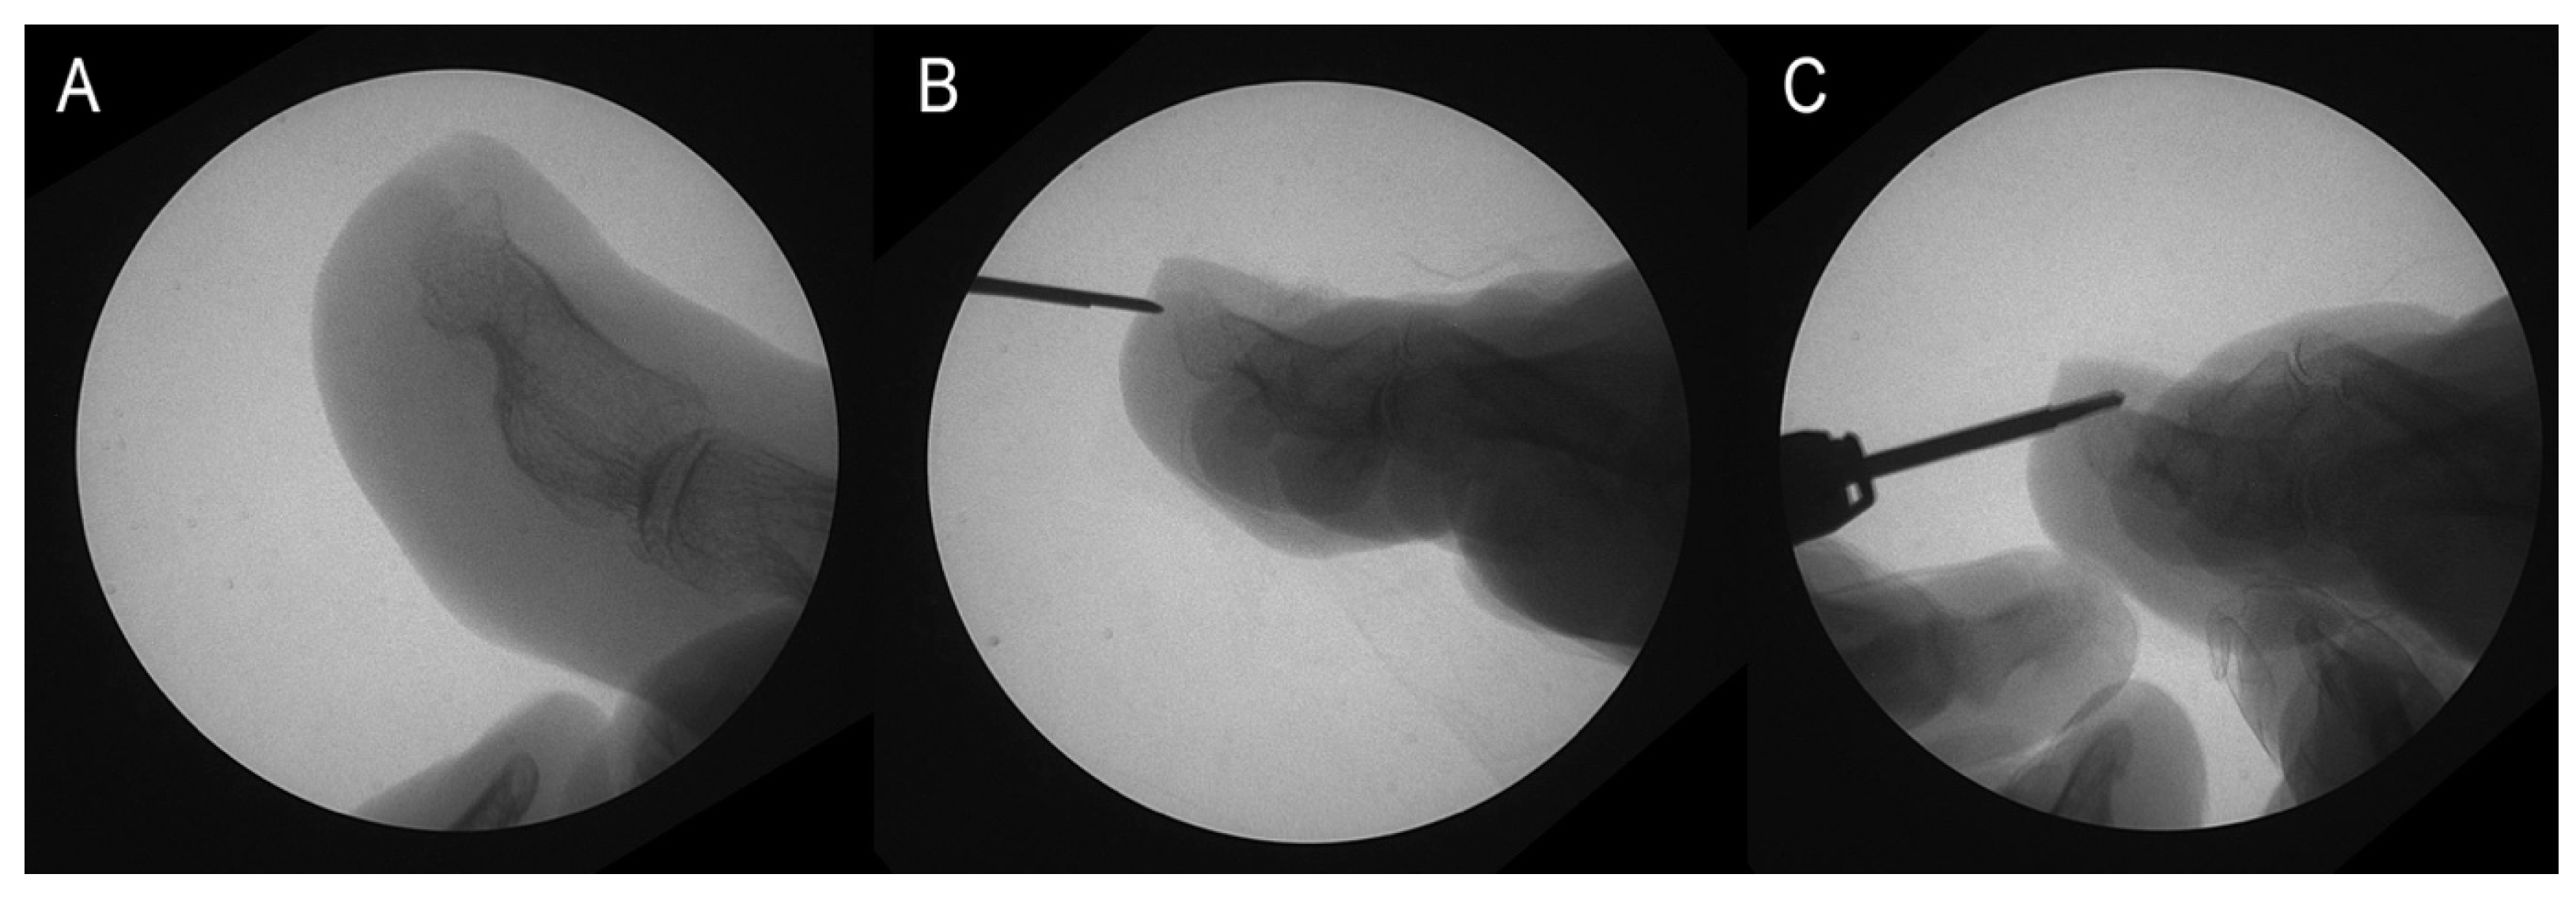

Additionally, the podiatrist objectively assessed each patient’s pain and categorized them into two groups: those who reported pain and those who did not. Patients with dorsal osteophytes who reported pain were advised to consider surgery for osteophyte removal during their initial visit (Figure 2A). After receiving comprehensive information about the available treatment options—including surgery and less invasive, non-definitive alternatives such as conservative management with orthotics or nail treatments—patients were given the autonomy to choose the approach they felt was most suitable. Surgery was recommended based on clinical factors such as symptom severity and lack of improvement with conservative treatments. However, some patients chose to avoid surgery due to personal preferences or a preference for less invasive options, a decision that was respected as part of the shared decision-making process with the medical team.

The surgery was performed according to the protocol outlined in [17] during the second visit, following these steps:

• A 2–4 mm incision was made using a Beaver-64-MIS scalpel on the distal surface wall of the toe, parallel to the longitudinal axis of the toe, followed by drilling of the osteophyte (Figure 2B).

• The contour of the osteophyte was defined using a blunt elevator to avoid damaging the nailbed.

• Osteotripsy was performed using medial and lateral movements of a mini-Shannon drill (Figure 2C).

• Pressure was applied with a surgical spoon to remove the bone paste resulting from the drilling.

Figure 2. Osteotripsy performance. (A) Surgical image. (B) Incision with no. 64 Beaver scalper. (C) Distal phalax osteotripsy.